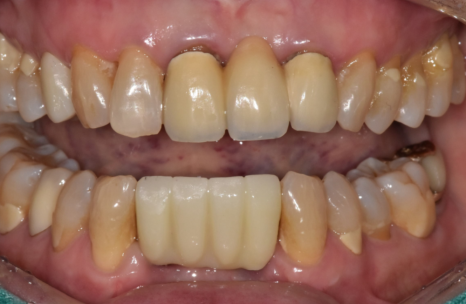

오늘은 70대 환자분의 솟구치고

흔들리는 치아 해결 과정을

케이스를 통해 설명해 드릴게요.^^

2년 사이 치아가 위로 솟고

흔들리게 된 이유

200727(왼) 221022 (오)

2년 전만 해도 뼈 상태가 양호하고

흔들림도 없으셨던 분인데,

2년 후 다시 뵙게 된 환자분은

아래 앞니 2개가 눈에 띄게 솟구치고

심하게 흔들리는 상태였습니다.

원인은 뿌리 염증으로

잇몸뼈가 녹아

지지력이 사라진 탓이었는데요.

마치 흙이 쓸려 내려간 나무가 들썩이듯,

뼈가 없으니 치아가 위로 밀려 올라온 것이죠.

이를 방치하면 결국

치아는 저절로 빠지게 됩니다.